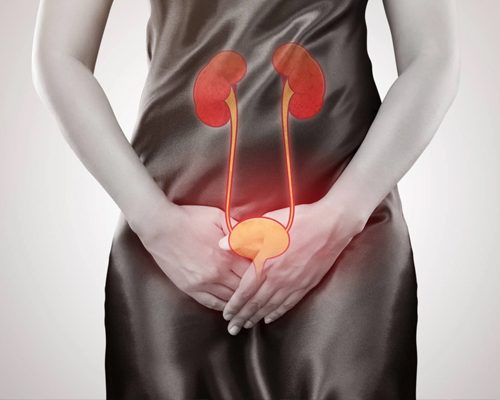

He had extensive and grounded training in dealing with management of patients with kidney stone disease, urological malignancies, male sexual dysfunction, urethral stricture disease, prostate related disease and Renal transplant. His training also includes management of simple and complicated UTI, Urosepsis, Neurogenic Bladder, OAB, UAB, Renal Trauma, urinary incontinence, female Urology, Bladder pain syndrome.